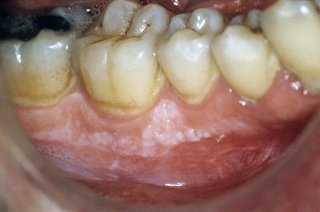

Close-up of a person's teeth and gums. There is a white patch on their gums, just below the teeth.

Some people get leukoplakia patches on their gums or on the floor or roof of their mouth.